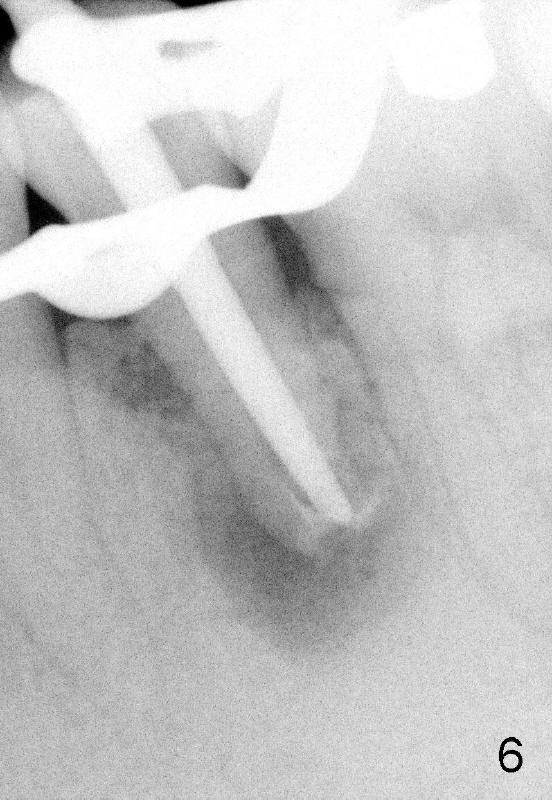

A 40-year-old Chinese man has periodic (once a month) mild pain and swelling in the lower left quadrant. Clinical exam reveals dens evaginatus (Fgi.1': <) in #20. Upon pressure from mouth mirror handle, there is limited amount of purulent discharge from the fistula (Fig.1": <). Preop PA shows a large canal with large periapical radiolucency (Fig.1). RCT started on Aug 6, 2010 with #70 file at 20 mm (Fig.2), #120 file at 16 mm (Fig.3) and CaOH paste in the canal (Fig.4). The dressing changed on Oct 8, 2010 (Fig.5). RCT finished on Jan 25, 2011 with master cone (rolled with several gutta perchae) (Fig.6), lateral condensation (Fig.7) and after vertical condensation and build-up (Fig.8). The canal was wet in the last two appointments with no sign of apexification. Follow up is done in 7 months (Fig.9), 11 months (Fig.10) and 18 months. Although the patient reports no pain after the treatment, the fistula remains with purulent discharge. The patient does not accept apical surgery. What should we do? Retreat with MTA (1,2,3)?